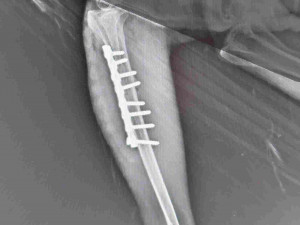

Nekroužkovaný mladý orel, vyvedený v roce 2019, byl na podzim odchycen s poraněným levým okem na lokalitě Tisová u Tachova. Orel měl problém s orientací a patologický nález na rohovce levého oka. Téhož dne putoval Záchranné stanice živočichů Plzeň. Tam si bohužel dravec přivodil při manipulaci nešťastnou náhodou nepříjemnou frakturu pravého stojáku.

„Kost praskla u těla tibiotarsus v horní části směrem ke stehenní kosti. Proto také 10. listopadu proběhla unikátní operace fraktury. O měsíc později jsme se pak s veterinářem Petrem Böhmem dohodli, že orla i s „železem“ v noze přece jen vypustíme zpět do volné přírody. Abychom však měli jistotu, že pták nemá žádné problémy, byl před vypuštěním vybaven speciální vysílačkou,“ řekl šéf záchranné stanice Karel Makoň. Orla vypustili v lokalitě Tisová  na Tachovsku u Modrého rybníka.